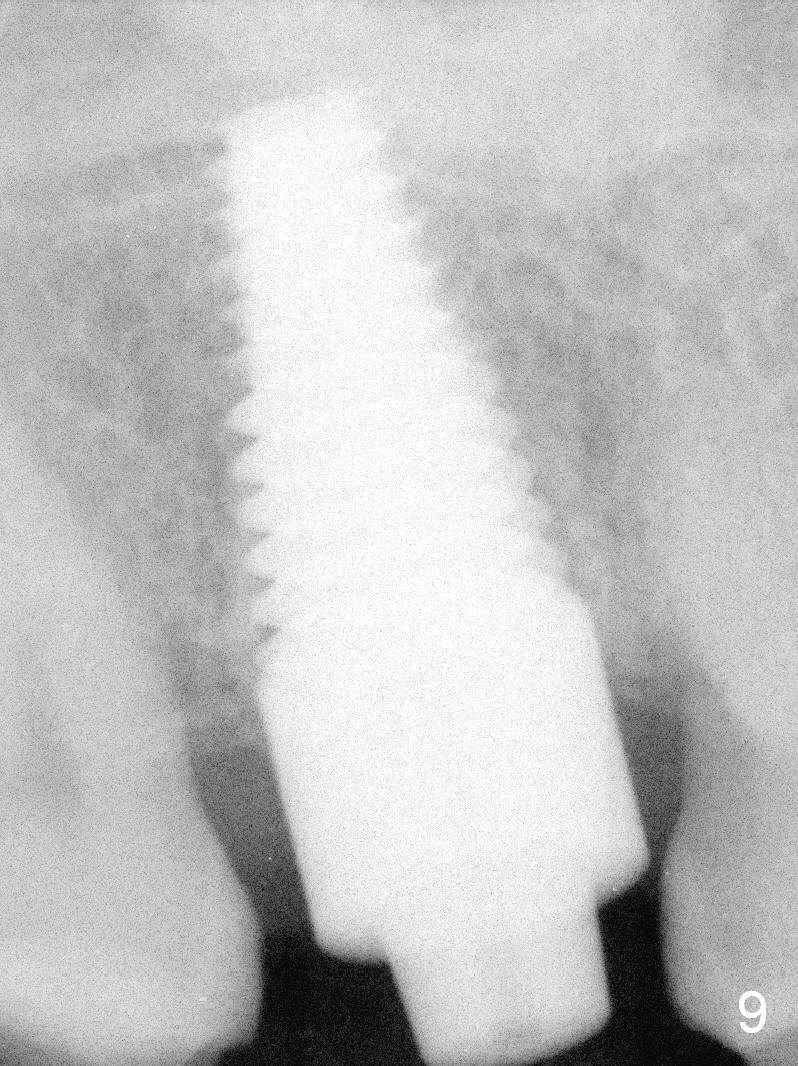

Sinus lift is done (Fig.9) before placement of 7x17 mm implant (I, >60 Ncm).  A 4.5x3 mm abutment is immediately placed for fabrication of an immediate provisional.

Implant threads appear to have embedded into the lamina dura.

The implant appears not to be placed apically enough, as compared to the design.  This leads to insufficient restorative space.